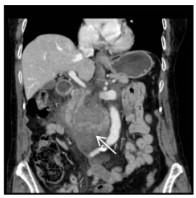

1 病例资料患者女,78岁,无明显诱因出现上腹部剧烈疼痛2 d入院,呈持续性,伴有恶心呕吐胃内容物数次、大汗淋漓、面色苍白、烦躁,否认既往高血压病史。查体:腹部叩诊呈鼓音,腹肌稍紧,全腹可及压痛,反跳痛(+/-),移动性浊音(+/-),肠鸣音弱。急诊查腹部CT示中腹部腹膜后血肿(图 1),考虑肠系膜动脉破裂可能,血肿大小约8.0 cm×4.6 cm,血红蛋白84 g/L,血压146/81 mmHg(1 mmHg=0.133 kPa)。外科专家会诊认为开腹治疗难度大,风险高,且患者及家属心理压力大,拒绝开腹手术。腹痛自行稍好转即出院。1周后患者活动时再次出现突发疼痛,症状与1周前相同。返回急诊科,经高风险谈话后接受了微创血管腔内治疗。

| 图 1 CTA发现腹腔巨大血肿,伴有瘤腔内对比剂强化(箭头示) |